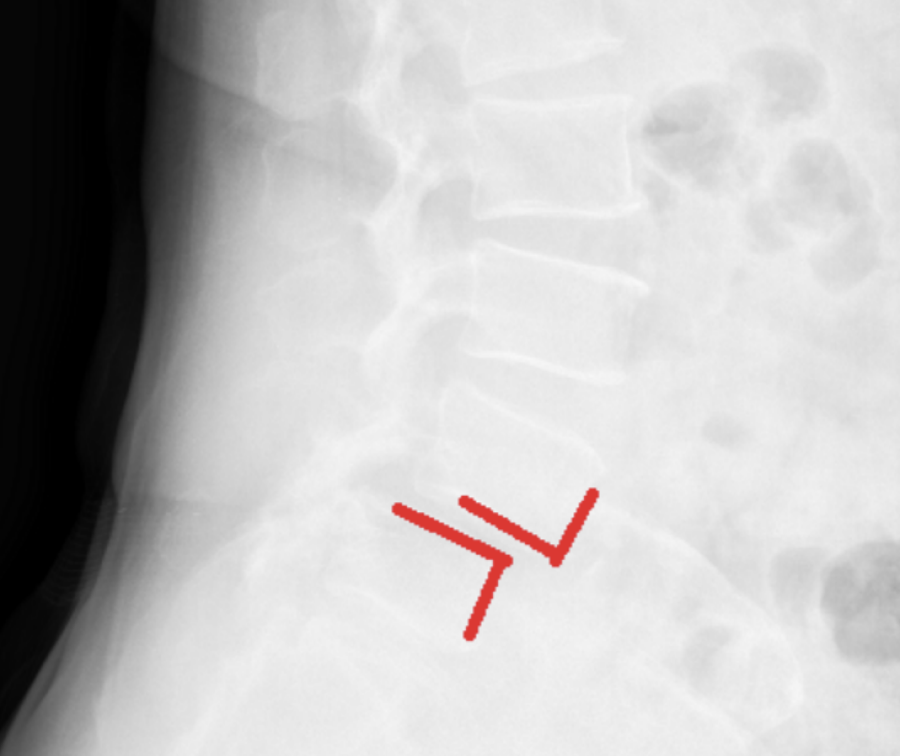

Radiografii din incidenţa laterală preoperator si postoperator ale unui pacient cu spondilolistezis L3-L4 si stenoza lombara multietajata ce a suferit o intervenţie chirurgicală de decompresie şi fuziune intercorporeala anterioara si laterala retroperitoneala cu cage-uri si fixare cu şuruburi pediculare L3-S1. Pe imaginea postoperatorie se observa corectia spondilolistezisului, refacerea lordozei lombare fiziologice, decompresia foraminala indirecta prin cresterea diametrului gaurilor de conjugare.